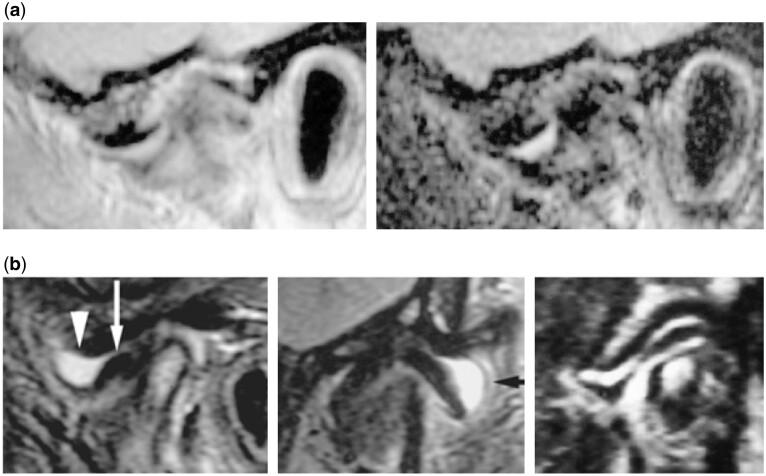

In this pictorial review, an introductory paragraph emphasizes the significance of some anatomical aspects for optimal imaging of the temporomandibular joint (TMJ). The most frequent pathologies: internal derangement (ID) and osteoarthritis (OA) are comprehensively discussed and illustrated. Less common conditions: ID and OA-like changes in children and adolescents, idiopathic condylar resorption, inflammatory arthritis, and juvenile idiopathic arthritis are briefly discussed. A short paragraph on differential diagnostics in young patients is included followed by a brief comment on expansile lesions that occasionally may occur in the TMJ.